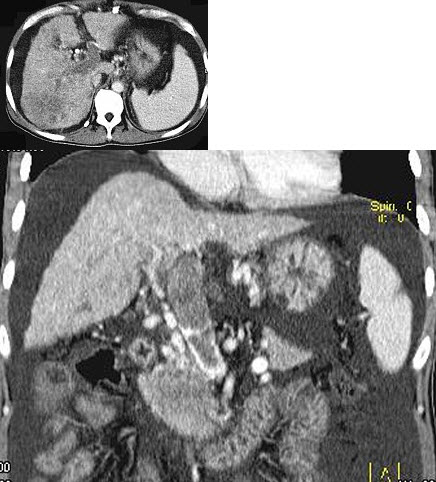

女,40岁,腹痛、腹泻、脓血便、里急后重,结合图像,选择最可能诊断( )

A:假膜性肠炎

B:结肠克罗恩病

C:结肠结核

D:慢性溃疡性肠炎

E:结肠淋巴瘤